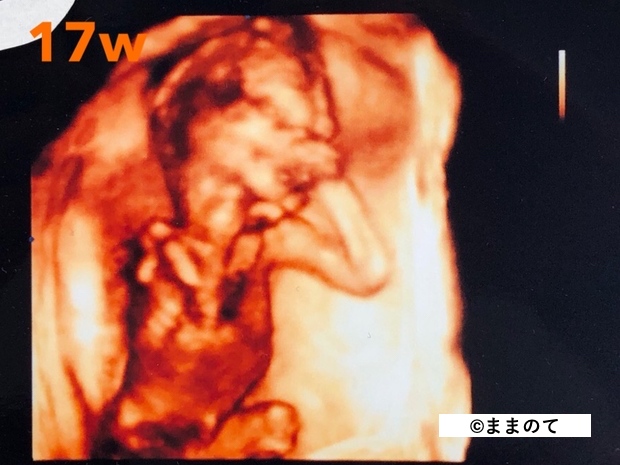

妊娠5ヶ月(16・17・18・19週)

赤ちゃんの性別がはっきりしてくるため、早ければエコー写真に外性器が写ることがあります。手足を動かすこともあり、人によっては胎動を感じ始める時期です。

赤ちゃんの身長は約25cm、体重は約250gになります。メロンほどの大きさが目安です。